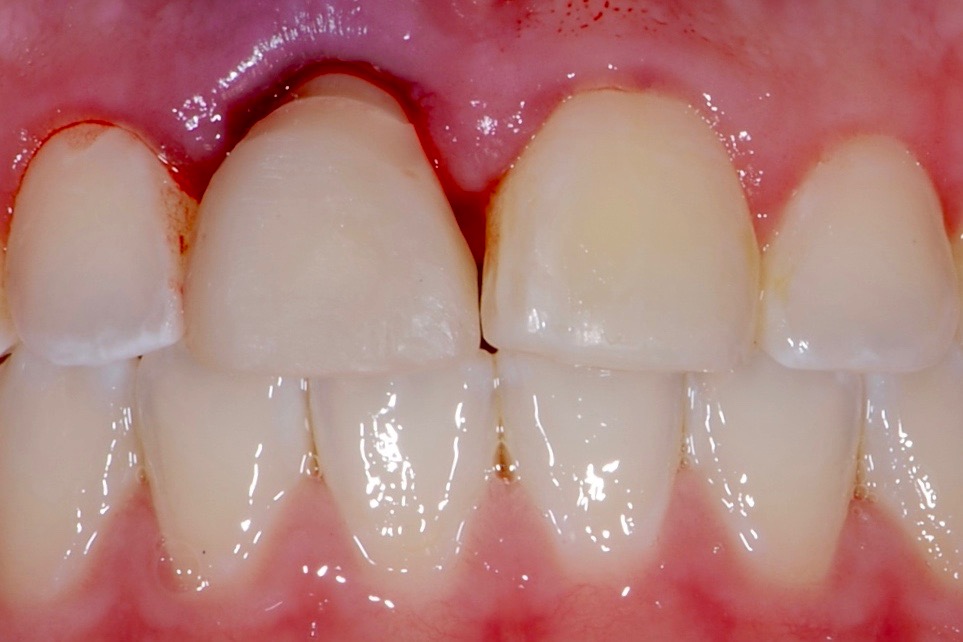

Fig 12. Clinical presentation of healed soft tissue and final custom abutment No. 8 placed on the day of the implant surgery 3 months prior.

Figure 12

Plugging into digital workflows provides opportunities to integrate CAD/CAM technologies at every step of the treatment process for dental implants. In another example, a patient presented with a failing tooth No. 8 (Figure 6 and Figure 7). After discussing treatment options, the patient chose to forgo any treatment to address tooth and soft-tissue asymmetries and wanted to proceed with a dental implant-supported restoration without additional treatment. After integrated 3-dimensional planning, the tooth was extracted, and then an implant and the final custom CAD/CAM abutment (titanium base with zirconia supra-structure) were placed with a provisional restoration in the same visit (Figure 8 and Figure 9). Soft-tissue grafting was also done at the same visit to address the deficient buccal tissue height on No. 8 (Figure 10). At 3 months, the patient presented for the final restoration, with excellent healing around the implant (Figure 11) and soft-tissue healing guided by the custom abutment (Figure 12).